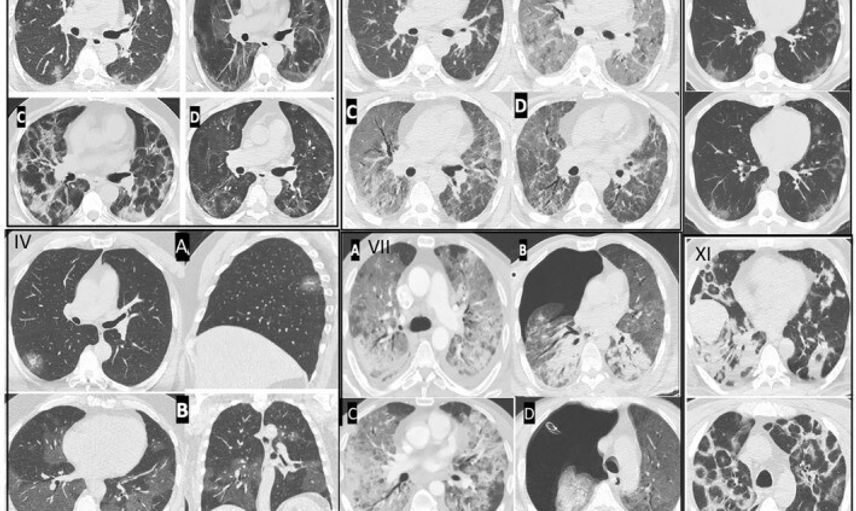

Göğüs Hastalıkları Uzmanı Prof. Dr. Şevket Özkaya, pandemi sonrasında genç yaşta görülen ani ölüm vakalarında artış tespit ettiklerini belirtti. Özkaya, bu artışın nedeninin Kovid-19 virüsünün damarlarda oluşturduğu kalıcı hasar olduğunu vurguladı.

Kılcal damar hasarı ve endotelit

Prof. Dr. Özkaya, pandemi boyunca takip ettikleri binlerce hastada damar iç yüzeyi hasarı yani endotelit saptadıklarını ve bunun ani ölümleri tetiklediğini ifade etti. Özkaya, Avrupa Kalp Dergisi verilerinin de bu durumu "Kovid-19 sonrası damar yaşlanmasının hızlanması" olarak tanımladığını belirtti.

Özkaya, Kovid-19’u geçirenlerde damar yaşının takvim yaşından daha yaşlı hale geldiğini ve bunun bazı kişilerde 5 yıllık yaşlanmaya eşdeğer olduğunu aktardı. Bu değişimin özellikle kılcal damar düzeyinde ciddi işlev bozukluklarına yol açtığını söyledi.

Özkaya'ya göre Kovid-19 geçirmiş ve pandemi öncesi yaptığı ağır sporları aynı şekilde sürdüren gençlerde yoğun egzersiz sırasında ani kalp krizleri görülebiliyor. Bunun nedeni, Kovid-19 sonrası kalp ve akciğer kılcal damarlarındaki hasar yüzünden yeterli oksijenlenmenin sağlanamaması; bu durumun nadiren de olsa ani ölüme kadar varabildiği ifade edildi.